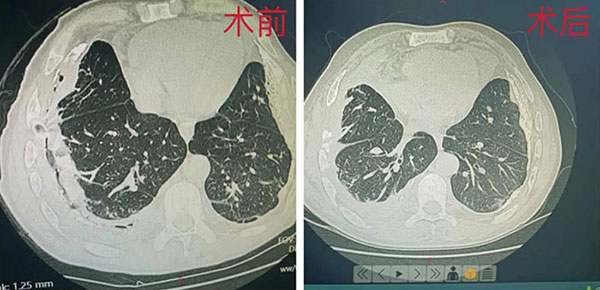

包裹性脓胸需要进行纤维板剥脱手术,以期达到解除对肺脏的束缚,消除残腔进而早期拔管,来促进肺功能恢复和早期康复。看到这位患者的CT后,发现了几个严重的问题:一是包裹范围非常大,从胸顶一直到膈肌,一个切口可能无法全部解决疾患;二是脓腔四壁已经明显钙化增厚,手术中可能创伤较大导致大量出血,患者本身已经有贫血、低蛋白血症,他能不能抗得住这么大的创伤在每一位专家心中都打了一个大大的问号;三是剥肺表面的纤维板时,可能造成肺的大面积损伤,术后会不会长期漏气,需要长期带管也摆在医者面前。

术后的护理一点不比手术简单。由于语言不通,医生查房时要求患者多活动、多咳嗽、多进食的医嘱,贯彻得并不好。护士们就用肢体语言让患者明白如何配合康复。每次巡视时让患者跟着自己咳嗽,患者不愿下地则直接将其搀起,带着他在走廊散步。经过微创中心医护人员的悉心照料,患者右肺完全复张、残腔消失,身上的管子也逐渐拔除,患者基本恢复了自理能力。